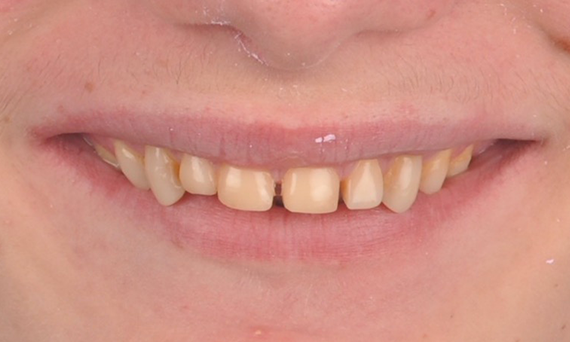

A particular and protracted case of skeletal Class II malocclusion and generalized amelogenesis imperfecta in a teenager was referred for prosthetic rehabilitation. The aim of the treatment was to prepare the remaining tooth structure, remove undercuts, and make room for all-ceramic crowns covering the entire dentine and simulating the lost enamel.

Before: Initial situation prior to orthodontic treatment.